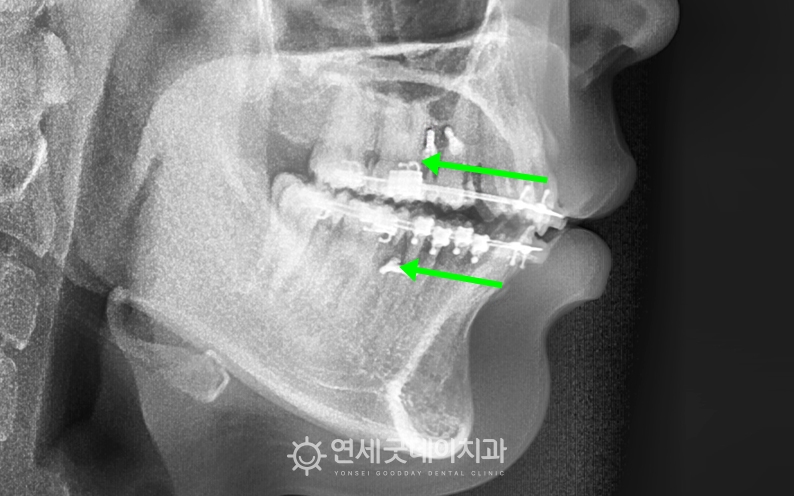

▲ 치료 전 엑스레이 (촬영시기 : 2023년 8월)

엑스레이를 보면 하악에 비해 상악의 전방돌출이 심하고

상악에 미니스크류를 식립하여 고무줄을 걸어

아랫니 보다 윗니가 다소 돌출되어 있었기 때문에

무턱에서 턱이 길어지고 턱선이 살아나는 방향으로 개선되고 환자분처럼 전형적인 돌출입의 경우 발치했을 때